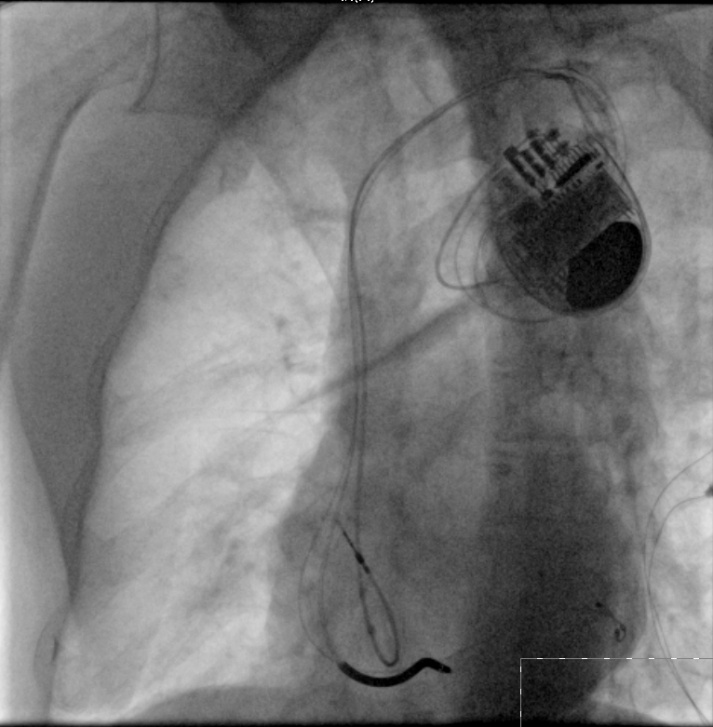

90歲的劉大爺,因為心衰反復(fù)出現(xiàn)呼吸困難及雙下肢水腫,心臟彩超提示左心室舒張末期內(nèi)徑達62mm(正常男性小于55mm),左室射血分數(shù)僅27%,心電圖提示竇性心律,完全性左束支傳導(dǎo)阻滯,單純藥物治療后無效。在瀘州市中醫(yī)院心衰中心接受帶除顫功能的三腔起搏器植入術(shù)及規(guī)范的藥物治療并定期隨訪,現(xiàn)心臟彩超提示左心室舒張末期內(nèi)徑恢復(fù)到57mm,左室射血分數(shù)恢復(fù)到45%。目前,劉大爺散步、養(yǎng)花、做家務(wù)已經(jīng)沒有了呼吸困難,也沒有再出現(xiàn)雙下肢水腫及腹脹,也不用再頻繁住院,提高了生活質(zhì)量。

帶除顫功能的三腔起搏器植入術(shù)(CRTD)